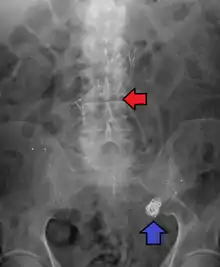

Abdominal aortic aneurysms are commonly divided according to their size and symptomatology. An aneurysm is usually defined as an outer aortic diameter over 3 cm (normal diameter of the aorta is around 2 cm),[16] or more than 50% of normal diameter that of a healthy individual of the same sex and age.[9][17] If the outer diameter exceeds 5.5 cm, the aneurysm is considered to be large.[15]

Abdominal aortic aneurysm involves a regional dilation of the aorta and is diagnosed using ultrasonography, computed tomography, or magnetic resonance imaging. A segment of the aorta that is found to be greater than 50% larger than that of a healthy individual of the same sex and age is considered aneurysmal.[9] Abdominal aneurysms are usually asymptomatic but in rare cases can cause lower back pain or lower limb ischemia.